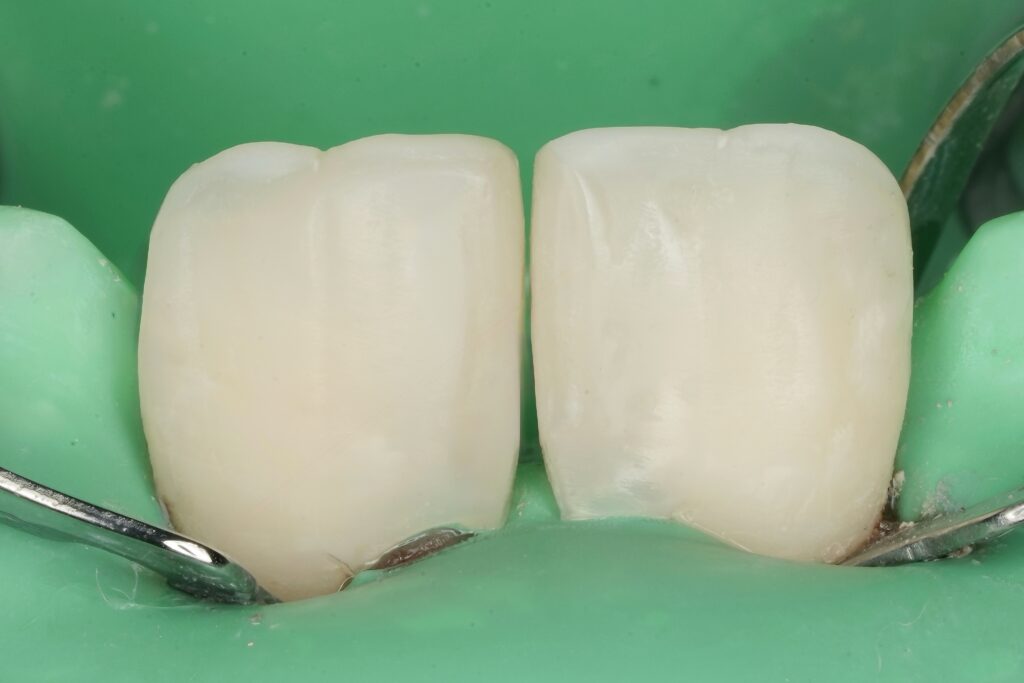

Step 6 – Finishing and Polishing

- Interproximal refinement for smooth contact

- Line angle definition for optical narrowing

- Multi-step polishing system to achieve enamel-like gloss

Surface texture was reproduced to mimic natural enamel light reflection.

Step 4 – Emergence Profile Development

One of the most critical steps in diastema closure is biological contour control.

- Proximal build-up performed incrementally

- Emergence profile designed to support papilla without overhang

- Contact point positioned strategically to prevent black triangles